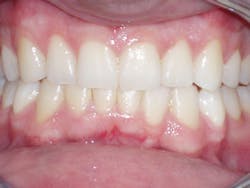

The six-week follow-up visits with Evin were eye-opening! I had the opportunity to observe his periodontal condition improve at each interval. After 30 aligners, or 15 short months, Evin's clear aligner orthodontic treatment was completed and final photos were taken. His bite was checked to confirm we had achieved our initial goal. Evin now had the appropriate overbite, overjet, and class I occlusion with proper posterior intercuspation with no interferences.

Figure 1

Retainers, similar to the aligners, but a medical grade heavier, were delivered to Evin and he was advised to wear them nightly.

Evin's treatment was completed in 2006. Fast forward nine years, and Evin schedules six-month preventive recare visits with our hygienist and still follows excellent home care. He has enjoyed nine years of health, comfort, and stability.